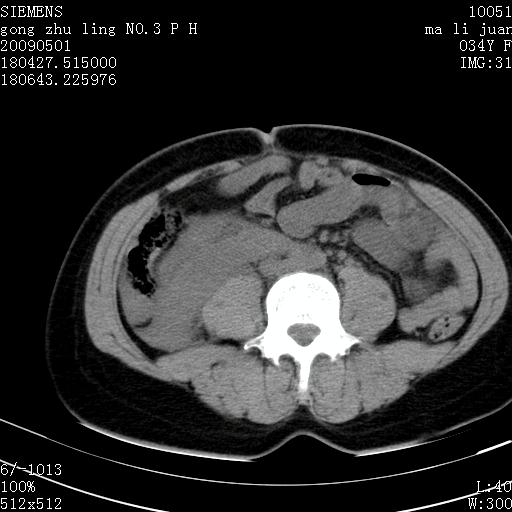

标题: CT19733:右肾碎裂 [打印本页]

标题: CT19733:右肾碎裂

青年女性,骑摩托车摔伤。

右肾碎裂伤,包膜下血肿。

术中仅见右肾碎裂,肾蒂血管未见断裂。